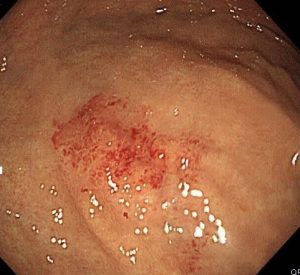

実際に胃カメラで、アニサキスを観察してみましょう。

胃の粘膜に、アニサキス虫体が頭を突っ込んで食いついています。

アニサキス虫体はとぐろを巻いています。

周りの粘膜は、炎症を起こして真っ赤になっています。痛々しいですね。

無事に除去できました(^^♪